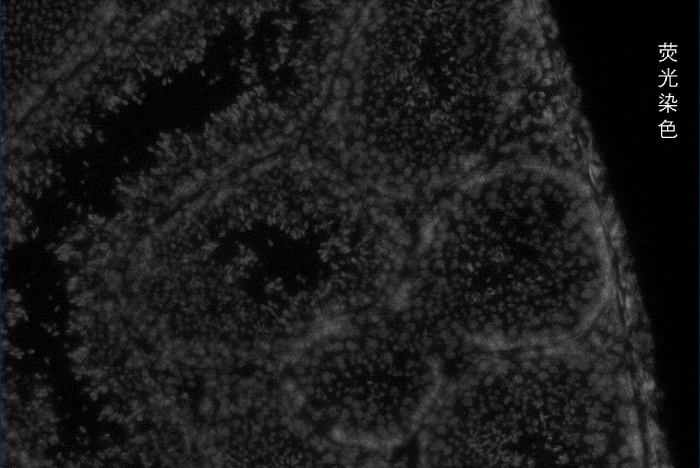

百創(chuàng)智造基于S系列空間芯片的底層設(shè)計,可以得到完全沒有錯誤的原片熒光圖像以及H&E圖像且與芯片完全對齊?;跓晒膺M行細胞核的定位刻畫細胞核的邊界;基于HE的校準輔助刻畫細胞的邊界,通過邊界信息映射到芯片上,提取相應(yīng)位置的測序數(shù)據(jù),實現(xiàn)精準的單細胞分割。

2.原片熒光染色+原片H&E染色+原片空間測序相結(jié)合技術(shù):既可以進行表達芯片H&E染色,又同時可以再表達芯片上進行熒光染色,保證細胞分割更準確。

答:首先需要有一個足夠高分辨率的空間芯片,這個我們在去年的時候就已經(jīng)解決了,其次是如何去精準的識別細胞,隨著分辨率的提升對圖像的準確度要求也越來越高,如何得到與芯片完全對齊的無拼接錯誤的圖像至關(guān)重要,我們通過不斷的摸索,基于S系列芯片的底層設(shè)計,解決了這個問題,得到完全沒有錯誤的原片熒光圖像以及H&E圖像且與芯片完全對齊,實現(xiàn)了精準的細胞分割